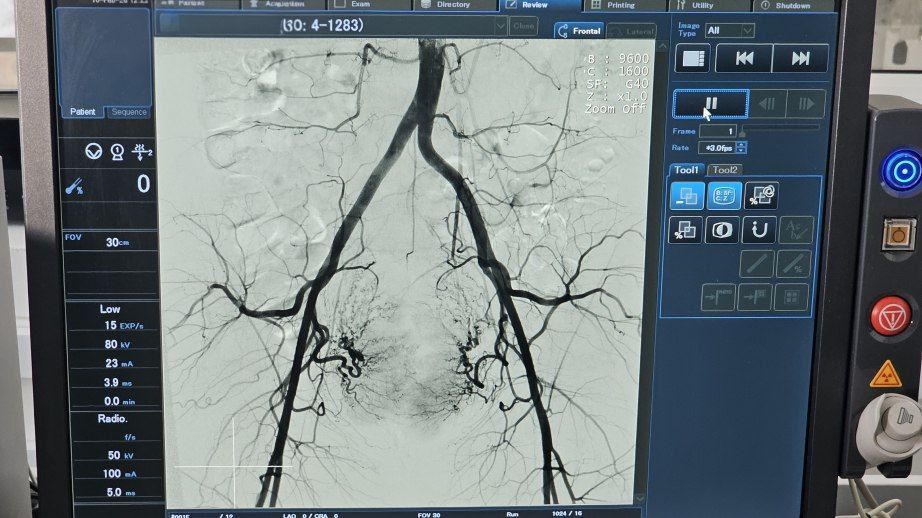

Благодаря постоянному обновлению оборудования растёт не только количество операций: диагностика и лечение становятся всё более эффективными и безопасными. За последние пять лет: восстановление пациентов ускорилось втрое, в три раза чаще специалистам...

В 2026 году количество квот на высокотехнологичную медицинскую помощь в онкоцентре Хабаровска возросло более чем в полтора раза: с 600 случаев в прошлом году до 955 запланированных. Это произошло благодаря поставкам современного оборудования –...